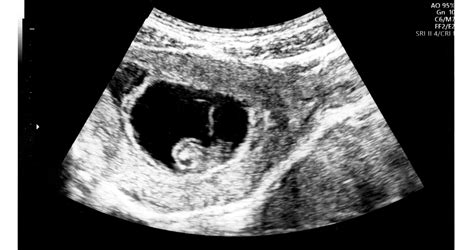

A magzat fejlődése és érzékelése

Már-már felfoghatatlan, milyen mértékű fejlődésen megy keresztül egy magzat a terhesség 9 hónapja alatt. Mindössze egyetlen sejtből indulva intenzív ütemben növekszik, egyre differenciáltabb sejtjei, majd szervei, testrészei alakulnak ki. Az embrió csíralemezeiből jön létre a szív, a csontok, a tüdő, fejlődik ki a máj, az érzékszervek, stb.

Hogy könnyebben el tudjuk képzelni, mekkora a baba a terhesség egyes szakaszaiban, gyakran mókásan gyümölcsökhöz, növényekhez hasonlítva jellemzik a kismamáknak szánt irodalmakban.

A 6 hetes orvosi vizsgálat alkalmával már hallható a baba szívverése. 9 hetesen alakulnak aprócska izmai, így képes mozgatni karját és lábát, 15 hetesen már kéz- és lábujjait is meg tudja mozdítani, ujját szájába veszi. Vizsgálatok szerint a 17-25. hét között a magzat már teljes mozgáskészlettel rendelkezik.

A 2. trimeszterre minden érzékszerv működik. 7 hetes korban már tapint, a bőrén keresztül érzékeli a rezgéseket. Méhbeli környezetét és saját testét is tapintással érzékeli. Az ízlelőbimbó és a szaglóhám kialakulásának köszönhetően 15 hetesen ízeket és szagokat érez. 4 hónaposan hall, a hangokra szívfrekvencia-változással reagál, illetve zárt szemhéján keresztül a fényt és a sötétet is észleli. A 26. héttől már a szemét is tudja nyitni, a fény észlelésekor szívritmusa csökken, mozogni kezd. Vizuális élménye az anya hasfalán keresztül áthaladó fények esetében hasonló, mint amikor kezünkkel eltakarjuk a villanó lámpa fényét.

Az ultrahangos vizsgálatok alkalmával jellegzetes arckifejezéseket és gesztusokat figyelhetünk meg. A vizsgálatok során mosolygást, undort, szomorúságot, fáradtságot, búskomorságot véltek felfedezni a kutatók. Mosolyt és sírást már az 5. terhességi hónapban detektáltak a kutatók. Emellett félelemre utaló jelzések is megjelenhetnek. Erre példa, amikor is magzatvízvizsgálat alkalmával a magzatburokba hatoló tűre a baba mozdulatlanná válik, ledermed, szívritmusa megváltozik. Ijedtség, félelem megélésekor a baba az anya szíve irányába törekszik húzódni, a szívverés hangja nyugtatólag hat rá, biztonságot jelent számára.